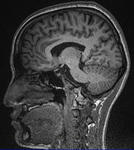

というわけで,3TfMRIの被験者をやって参りました.

そして,綺麗に撮れるものですね.

自分のやった3テラのものは,

診断用に一般使用されているものの倍

保険適用外ってやつで

流石に綺麗でした.

とはいえ

自分で見ても,なんのこっちゃですが.